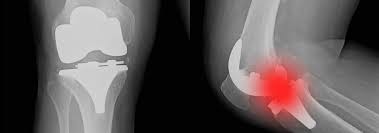

Prothèse articulaire

L’articulation usée est recouverte d’un implant qui lui redonne forme et mouvement.

Pour qui cette intervention est-elle indiquée ? les personnes souffrant d’arthrose symptomatique, c’est-à-dire qu’elle provoque des douleurs non maîtrisées par les antalgiques.

Avantages : procédure aux résultats nombreux et éprouvés avec succès ; réduit la douleur et améliore la mobilité, l’autonomie dans les activités quotidiennes et la qualité de vie.

Inconvénients : les prothèses sont des implants et, en tant que telles, elles sont sujettes à l’usure au fil des ans. Même si, à titre indicatif, plus de 90% des prothèses de hanche sont en place vingt ans après l’intervention, il convient de réaliser l’implantation au moment le plus opportun. L’avis du chirurgien est fondamental.